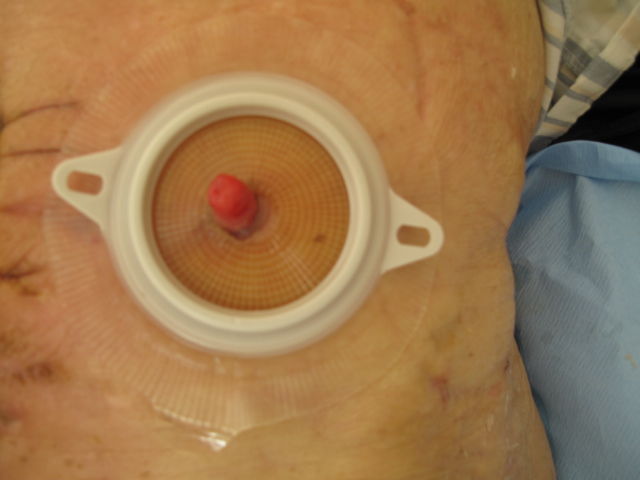

术后一个月,输尿管形成乳头(此为84岁高龄、哮喘、膀胱全切术后患者)

双侧输尿管乳头形成